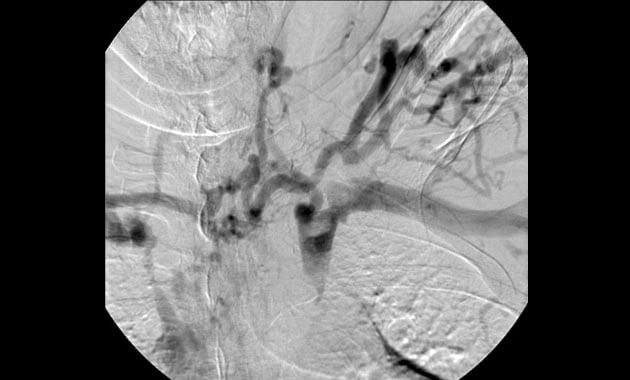

Vascular Malformation

- Conditions: Arteriovenous malformation (AVM), Hereditary Hemorrhagic Telangiectasia (HHT)

- Services: Angiography, embolization